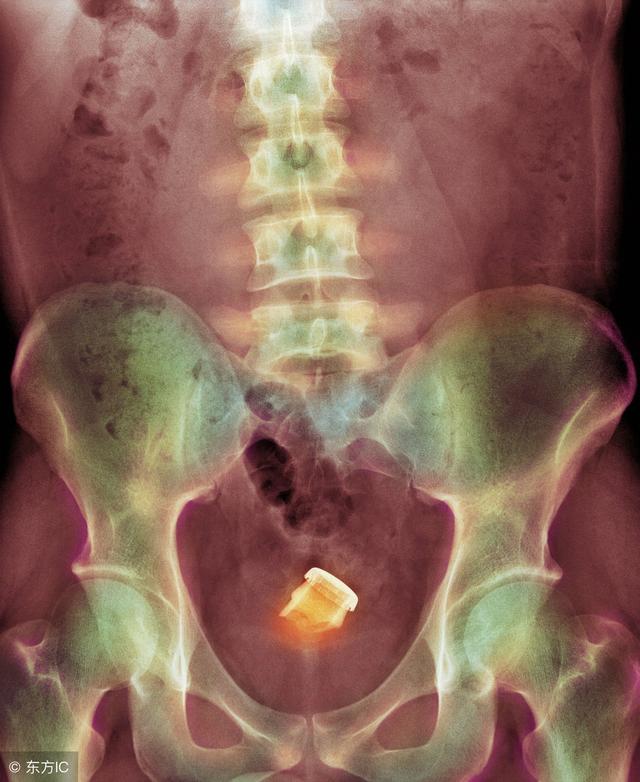

最近急诊科住了一名患者,因为直肠内异物被收治入院。直肠异物并不算什么罕见的事情,只不过这次的异物有点特殊:是个灯泡。

患者是个四十多岁的男性,由于各种原因,不慎将灯泡塞入体内无法取出。后因担心灯泡在体内破裂,故来就医。